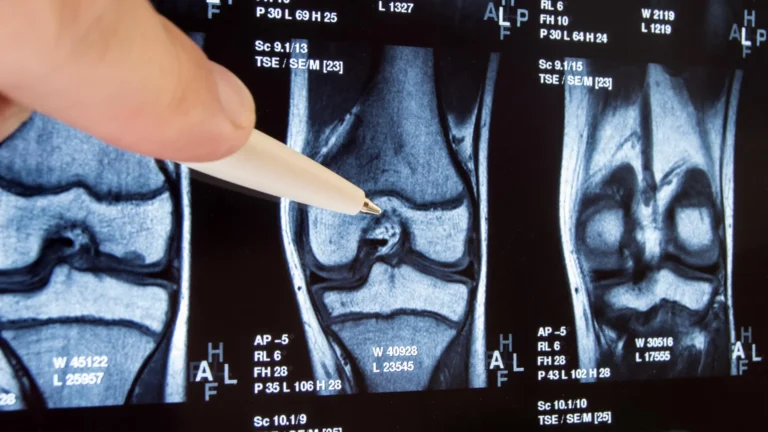

"These findings carry immediate and profound implications for how we approach patient care and surveillance in the aftermath of severe respiratory viral infections," stated Dr. Jeffrey Sturek, an accomplished physician-scientist at UVA and a key collaborator on this study. "For a considerable time, we have understood that factors like smoking substantially augment the predisposition to lung cancer. The outcomes of this current research suggest that we may need to re-evaluate severe respiratory viral infections with a similar level of concern. For instance, in certain patient populations identified as being at high risk for lung cancer due to their smoking habits, we routinely recommend close monitoring through scheduled low-dose computed tomography (CT) scans of the lungs to enable early detection. It is plausible that future research protocols will advocate for comparable screening strategies following severe respiratory viral infections."

The implications of this research extend directly to the critical domains of early detection and timely treatment of lung cancer. Dr. Sun and his colleagues aspire for their work to empower clinicians with improved tools to identify patients who may be at a heightened risk of developing lung cancer following severe respiratory infections. Earlier identification holds the promise of initiating therapeutic interventions sooner, thereby substantially improving patient prognoses and outcomes.